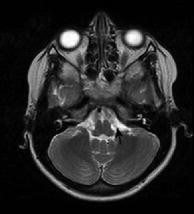

Facial nerve palsy in posterior fossa arachnoid cysts: report of two cases

Two patients with a posterior fossa arachnoid cyst responsible for isolated facial nerve palsy are reported.

The relationships between the cyst and the facial nerve and between the facial nerve palsy and the size variation of the cyst are discussed and documented by pre- and postoperative magnetic resonance imaging.

Fig. 4